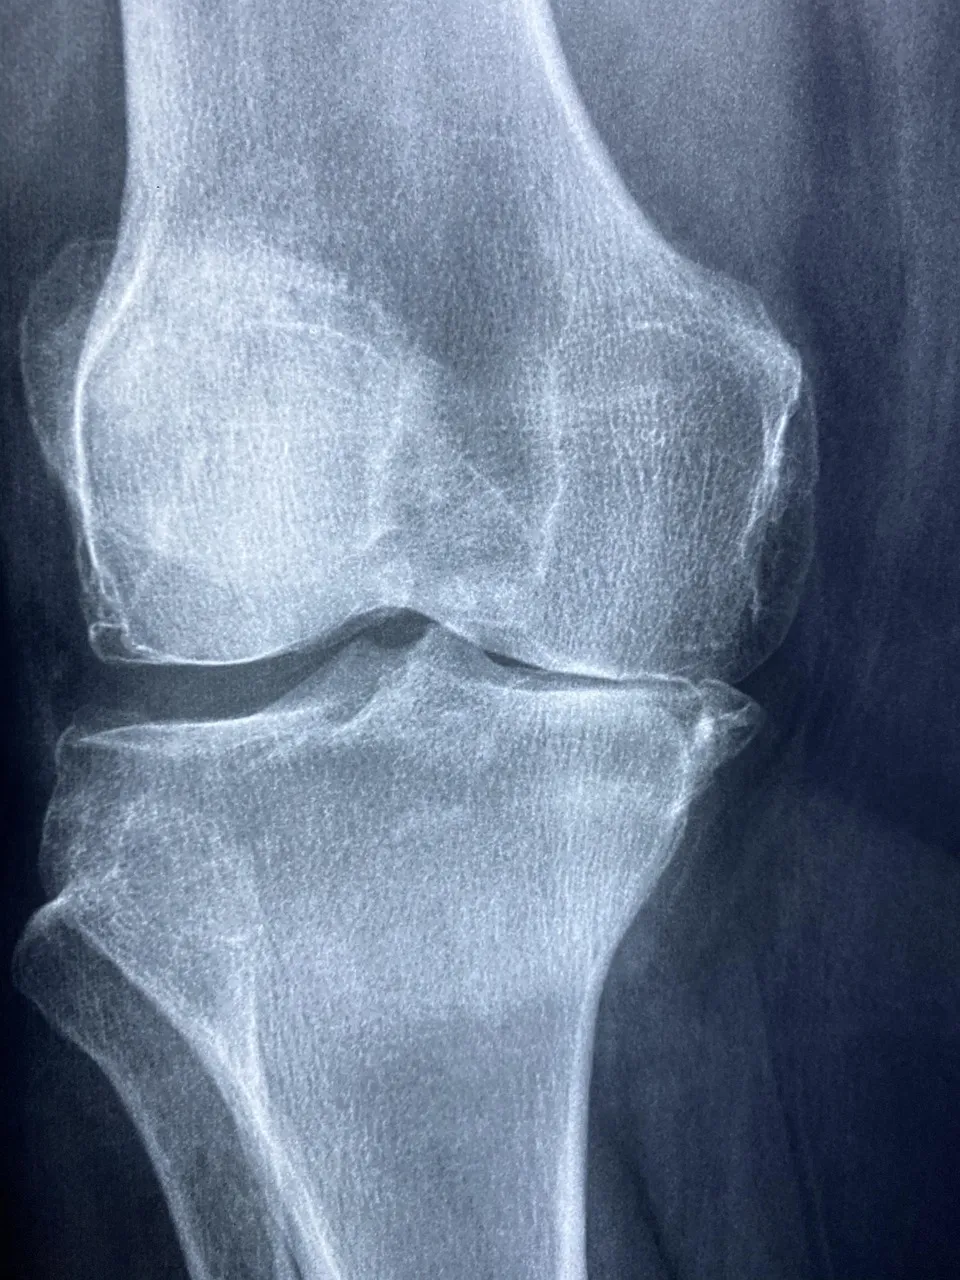

MSM 효능 1 관절 통증 완화

부모님이 MSM을 복용한 이유는 단연 무릎 통증 완화 때문이였습니다.

하루에 한 번 MSM 1,000mg을 식사 후 꾸준히 섭취하셨는데

2주 정도 지나자 “무릎이 덜 뻣뻣하다”는 말씀을 하시더라고요.

MSM 효능 중 가장 대표적인 것이 바로 관절 염증 완화와 통증 감소라고 합니다.

MSM이 염증을 유발하는 사이토카인 분비를 억제해주고, 연골의 손상을 막아주는 역할을 하기 때문입니다.

실제로 미국 임상 연구에서도 MSM을 12주간 복용한 사람들의 관절 통증 지수가 30% 이상 낮아졌다는 결과가 있습니다.